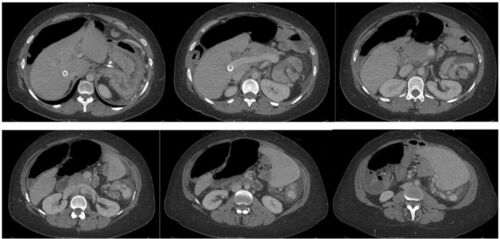

症例121:1週間持続する左上腹部痛が急激に悪化した37歳女性 (Am J Emerg Med. 2021 Mar;41:265.e1-265.e3.)

病歴/身体所見 ・37歳女性 ・潰瘍性大腸炎により結腸全摘術後、肝硬変を合併した原発性硬化性胆管炎、腸閉塞の既往がある ・7日前から嘔気を伴う左上腹部痛が持続していたが、急速に増悪したためER受診 ・BT37℃, HR107bpm, BP169/67mmHg, SpO2 100% ・中等度…